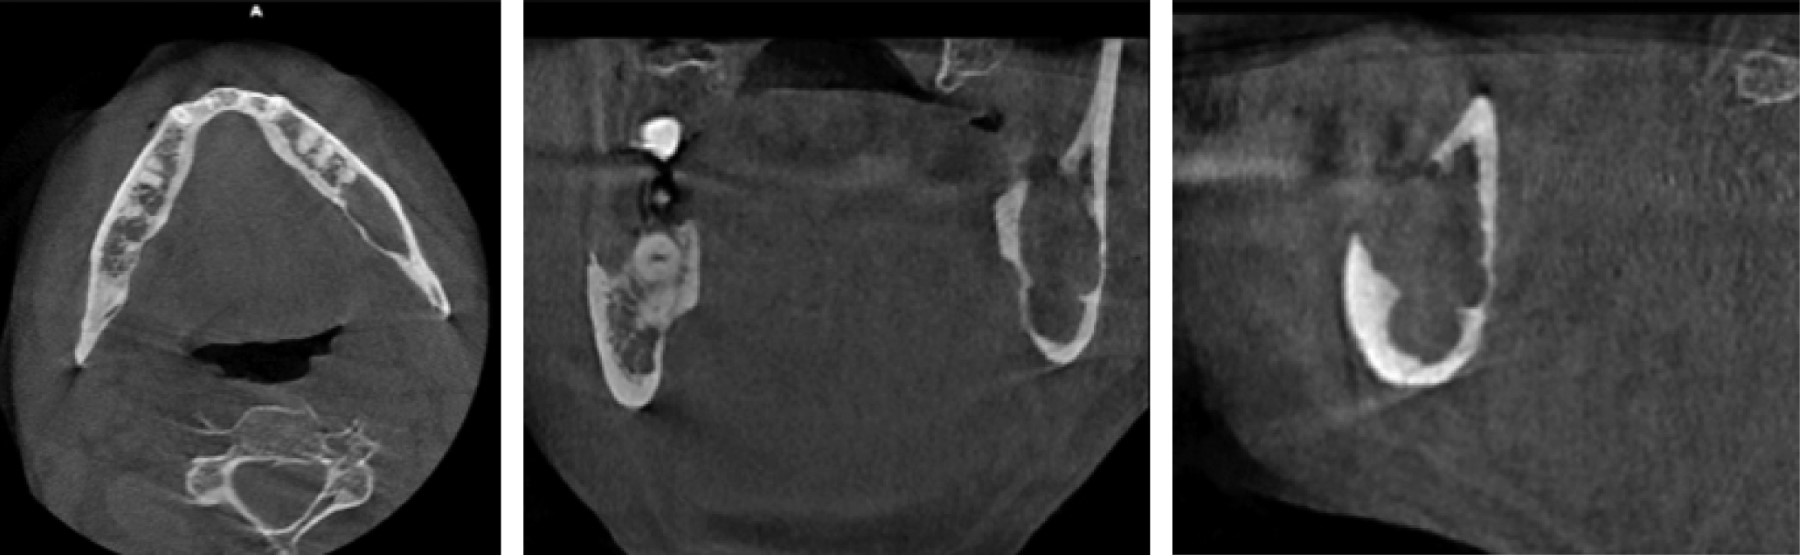

Se trata de paciente masculino de 54 años de edad y procedente de Caracas, Venezuela, quien refiere inicio de enfermedad actual en enero de 2023 posterior a ser intervenido quirúrgicamente para odontectomía de OD 4.8, en vista de presentar aumento de volumen en región paramandibular derecha, concomitante fuerte sintomatología dolorosa, acude a consulta. Al examen clínico maxilofacial, se observa asimetría facial a expensas de tercio inferior facial por aumento de volumen que involucra la región paramandibular derecha, indurado, doloroso a la palpación superficial y profunda, sin signos de flogosis. Al examen intraoral, se evidencia apertura oral disminuida, cuantificada en 15 mm, dentición permanente, oclusión estable. Alveolo de OD 4.8, en proceso de cicatrización, con capa de fibrina perialveolar, sin presencia de gasto purulento o signos de infección. Se indica ortopantomografía (Figura 1), la cual se recibe de mediana calidad técnica, donde se puede observar una imagen radiopaca en región basal de cuerpo mandibular derecho, compatible con resto radicular de OD 4.8, así como también una imagen radiolúcida sugestiva de lecho quirúrgico de odontectomía del mismo. Como hallazgo radiográfico, se puede evidenciar una imagen radiolúcida, multilobular, de bordes difusos, en región de cuerpo y ángulo mandibular izquierdo, por lo que se indica tomografía computarizada de haz cónico (Figura 2), donde en sus cortes axiales, coronales y sagitales se puede evidenciar una imagen isodensa de 4 × 3 × 2 cm multilobulada, de bordes bien definidos, con expansión de las corticales óseas en la región de cuerpo y ángulo mandibular izquierdo, en relación con los OD 3.6, 3.7. Asimismo, se observa una imagen hiperdensa en región de cuerpo mandibular derecho, compatible con resto radicular de OD 4.8. Se decide realizar intervención quirúrgica bajo anestesia local, para realizar toma de biopsia incisional en región de ángulo mandibular izquierdo, la cual reporta como resultado histopatológico: queratoquiste odontogénico (Figura 3).

Figura 2